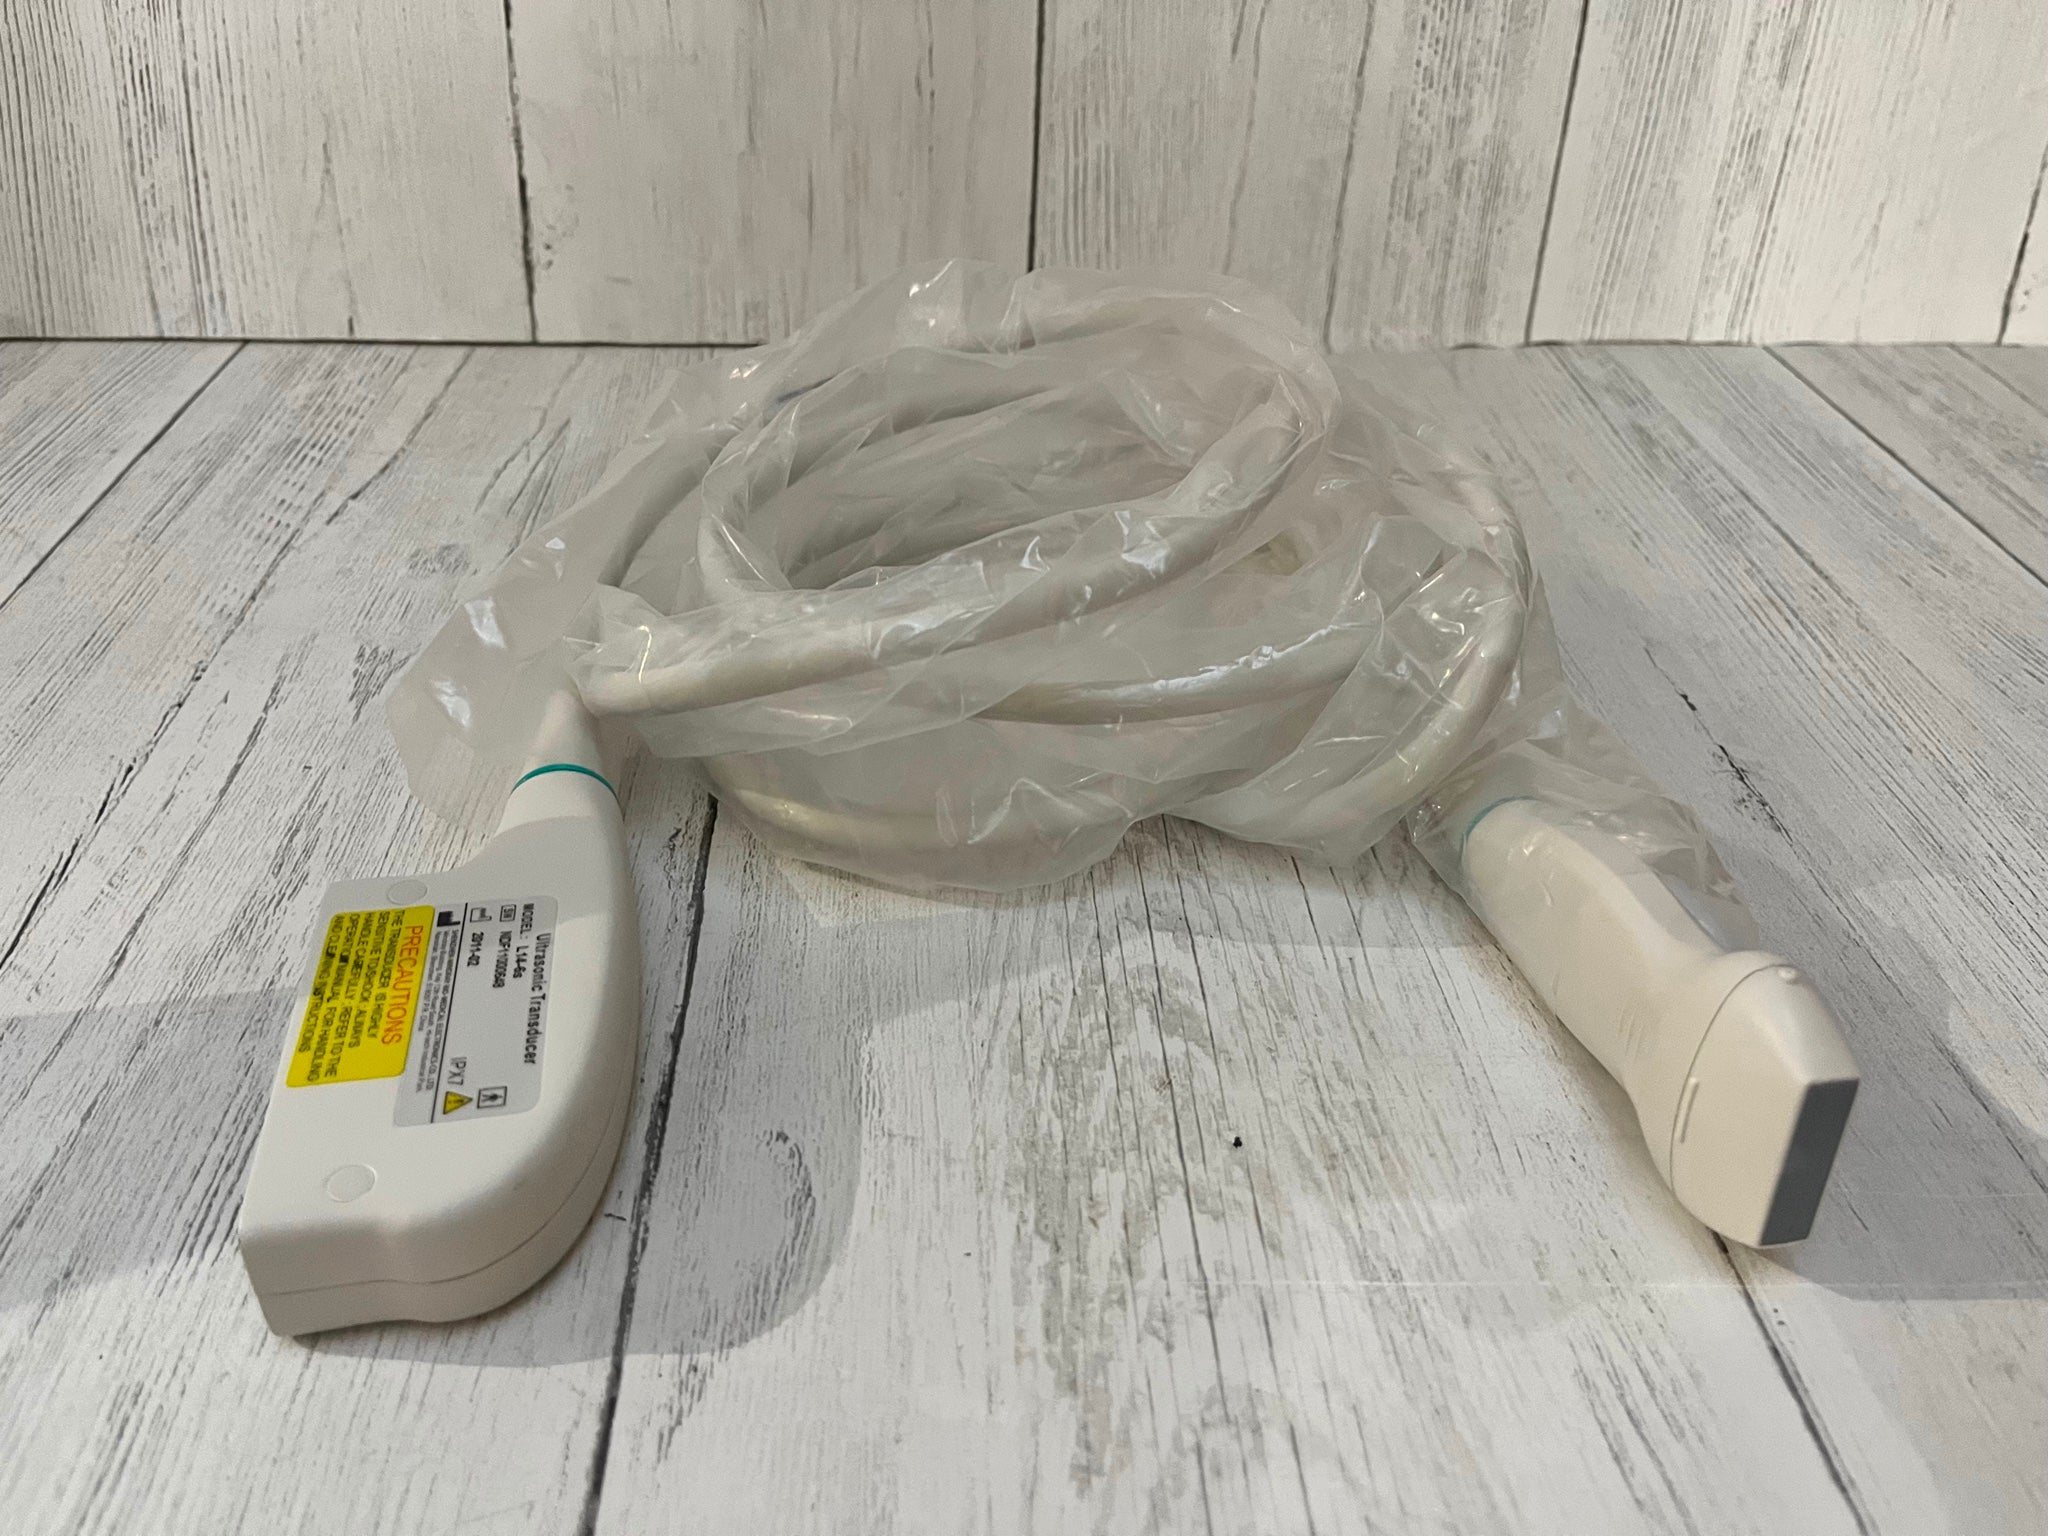

Convex(R60): C5-2Ds

- Application: Abdomen, Obstetrics, Gynecology, Kidney, Urology

- Number of element: 80

- Center frequency: 3.5MHz

- Working frequencies: 2 – 5MHz